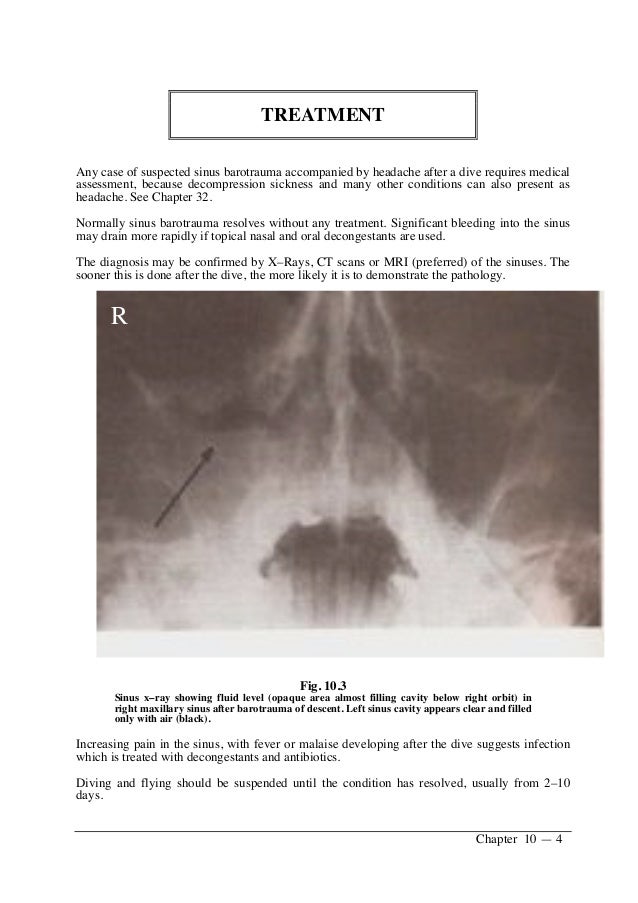

Figure 1 from Paranasal sinus barotrauma in sports selfcontained Sinus Barotrauma Flying Treatment What should i do to prevent. Medications such as analgesics or decongestants can be given to treat pain and discomfort. Recurrent sinus barotrauma due to anatomic derangement has been managed effectively with endoscopic sinus surgery. In most cases, aerosinusitis symptoms resolve within a few hours to a few days after the event that caused it (such as flying at high. Sinus Barotrauma Flying Treatment.